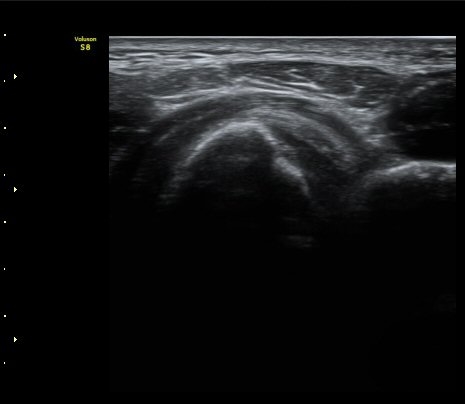

ÆÈ²ÞÄ¡ ¾Õ Ⱦ´Ü¸é°Ë»ç¿¡¼­ À̵ιڱÙÀÌ ÈûÁÙ·Î ÀÌÇàµÇ´Â °ÍÀÌ °üÂûµÈ´Ù(±×¸² 1, 2).

ŽÃËÀÚ¸¦ Á¶±Ý ¸»´ÜÀ¸·Î À̵¿ÇÏ´Ï À̵ιڱ٠ÈûÁÙÀÌ ¶Ñ·ÈÇÏ°Ô °üÂûµÇ°í ÇÔÁÙ ÁÖÀ§¿¡

¼ö¾×Àú·ù°¡  º¸ÀδÙ(±×¸² 3, 4, 5, 6)